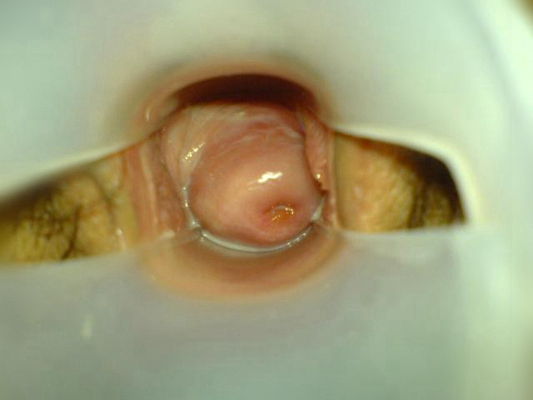

子宮頸炎圖片

宮頸炎